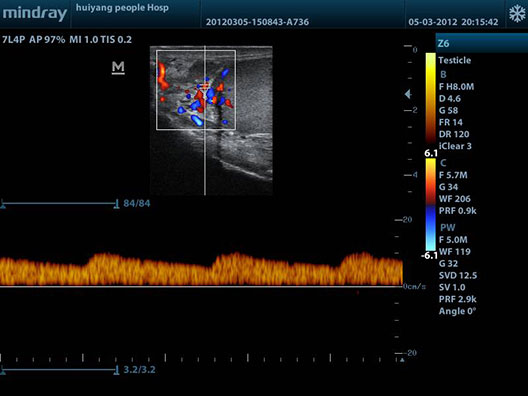

Se dispone de un Ecógrafo Mindray Z6 multifrecuencia de última generación con gran definición y resolución de imágenes.